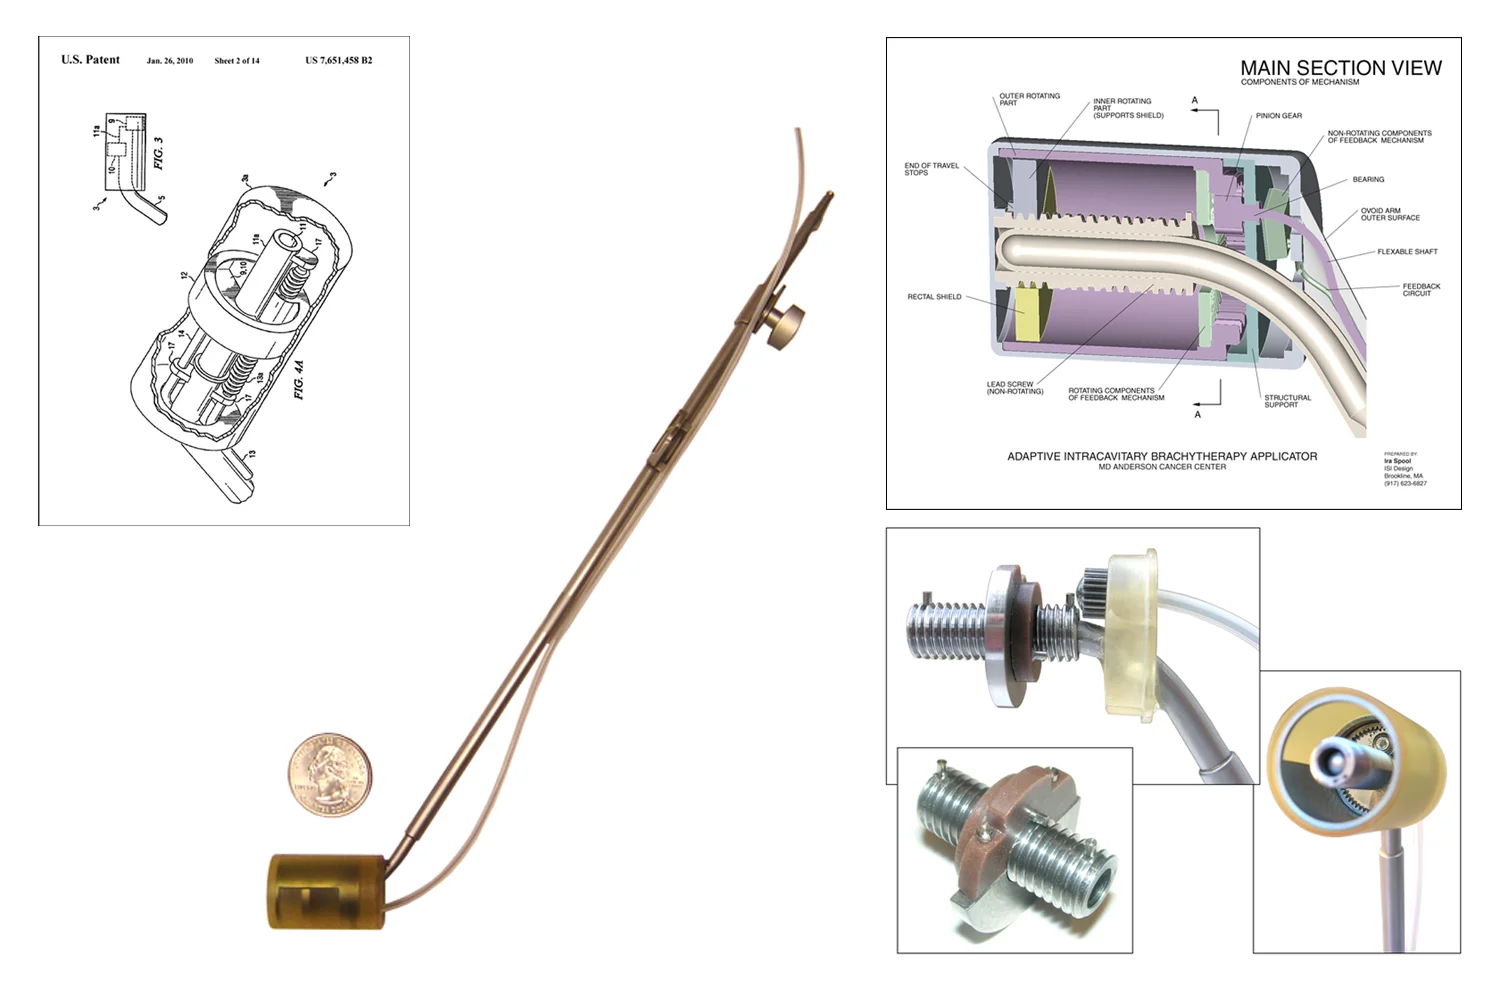

Intracavitary Brachytherapy Applicator

nucletron bv

Designed and developed innovative medical devices for radiation oncology. Our team included myself, a radiation oncologist, a radiation physicist, and a chemist. The project shown above is the “Adaptive Intracavitary Brachytherapy Applicator” for the treatment of cervical cancer. Received a patent for its internal mechanism which allows the radiation shielding to be adjusted for each patient. The device was licensed by a multinational medical device company based in the Netherlands (Nucletron BV). Patent #7651458, “Adaptive Intercavitary Brachytherapy Applicator”.